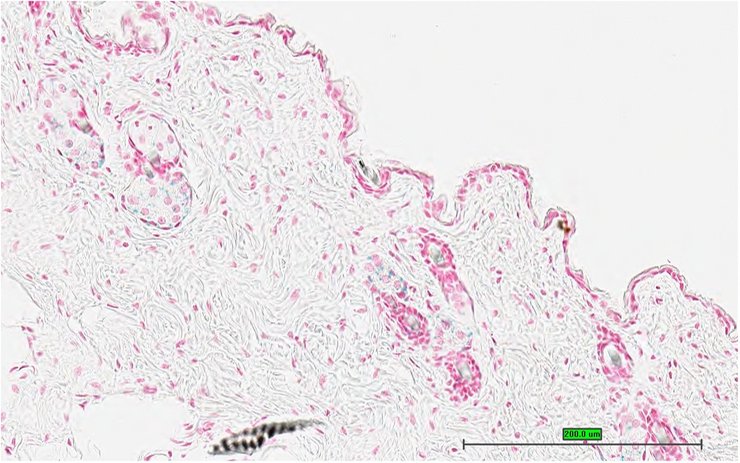

TS28: skin Present UC Davis_1865392